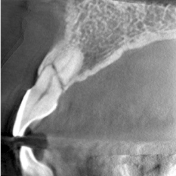

根管END

-

70μm(Voxel Size)高精細モード搭載

End、根尖、破析、分岐部病変など精細読影をサポートします。

CT撮影時、Free FOVで撮影に必要な領域を絞り込み、

的確に高解像度70μmの世界トップレベルのCT画像を再現します。-